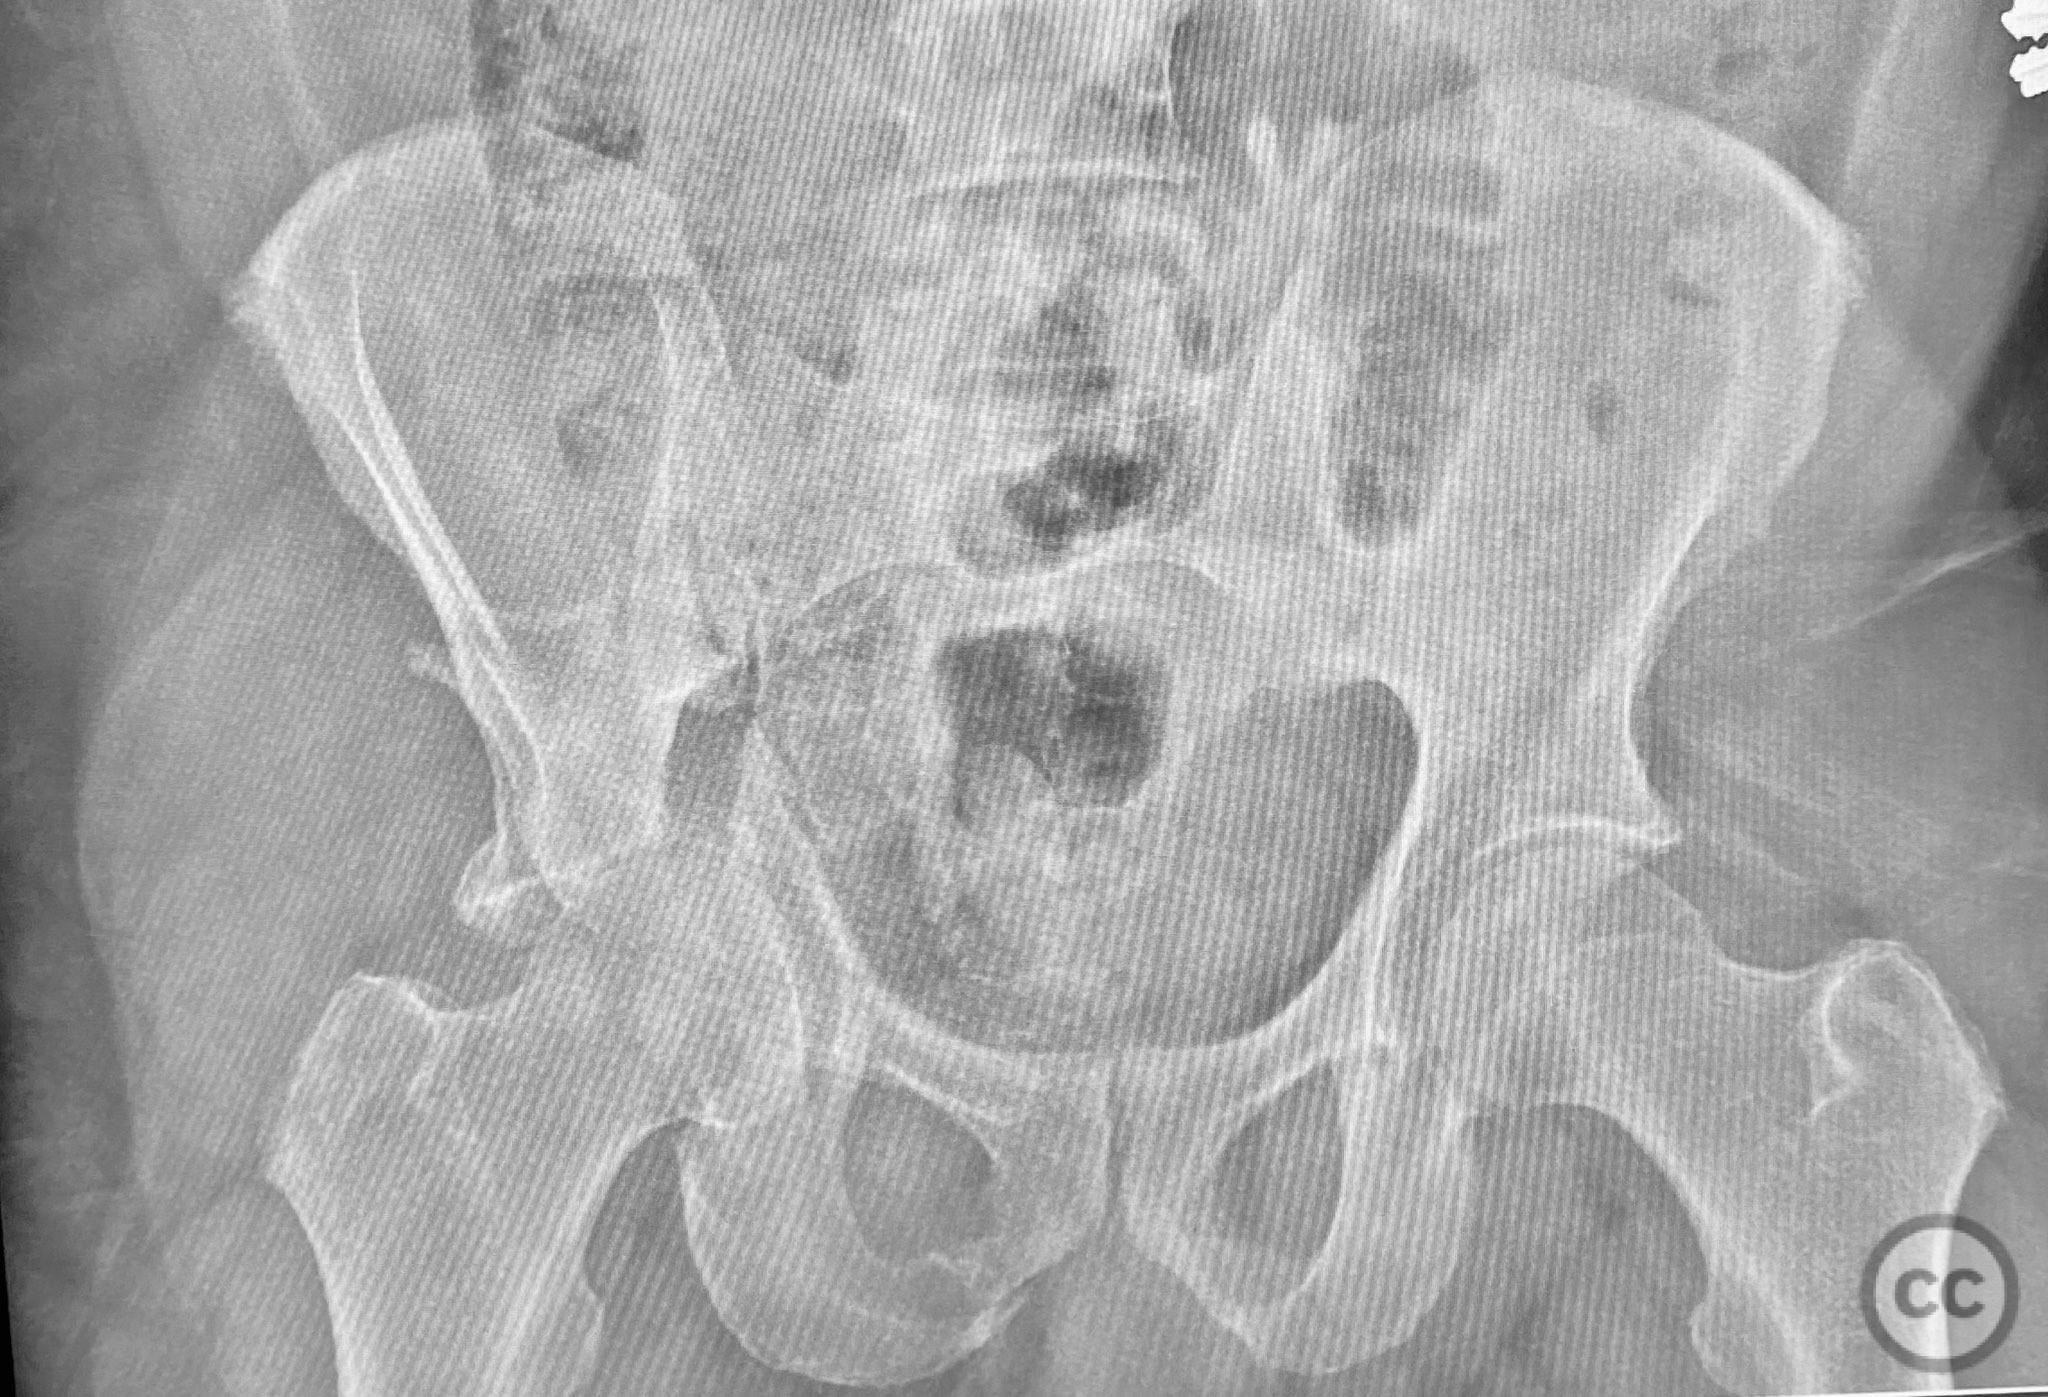

Clinical and radiological findings:  A patient presented with a combined anterior column and posterior hemi-transverse (AC/PHTr) acetabular fracture. Plain radiographs demonstrated multiple displaced fragments involving the acetabular dome and femoral head region, with clear disruption of the anterior column and posterior transverse components. Advanced imaging, including axial and coronal CT, provided detailed visualization of cortical surface displacement, fragment orientation, and associated soft tissue status. The edge of the intact dome and femoral head injuries were identified, as well as a residual defect at the edge of the dome following reduction. AO/OTA classification: 62B2 (anterior column with posterior hemitransverse).